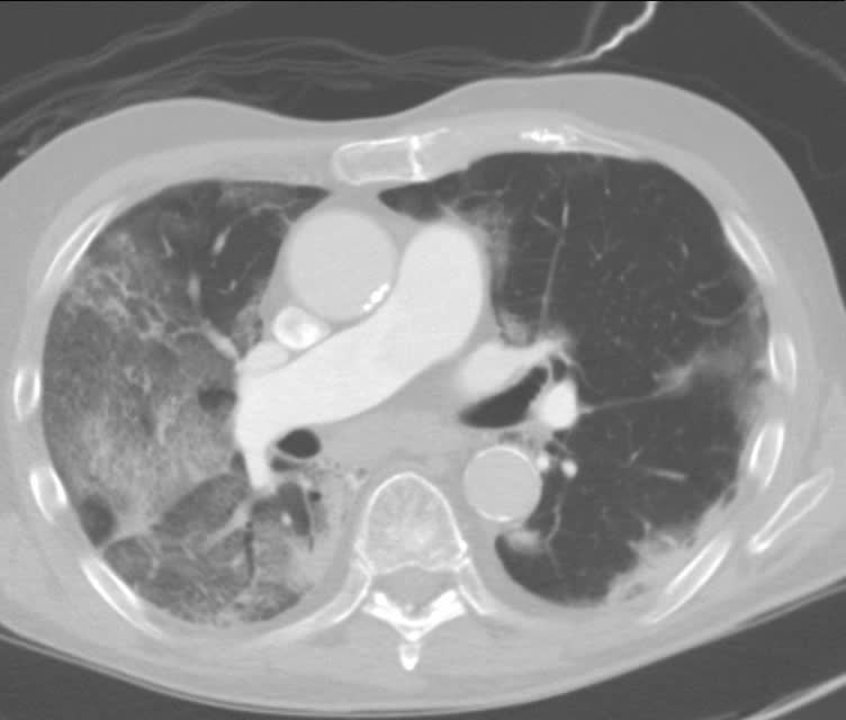

Chest Ct Scan During Invasive Pulmonary Aspergillosis A Chest Ct Download Scientific Diagram